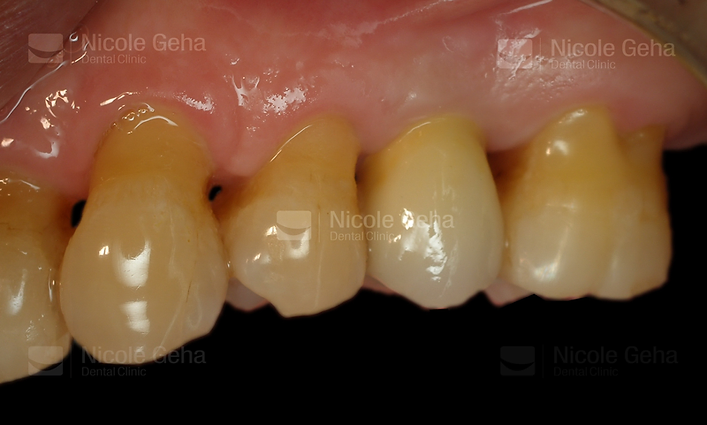

SINGLE IMPLANT

case 1: before

After